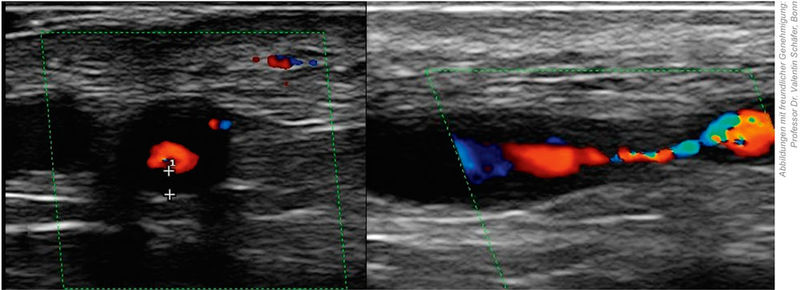

In den aktuellen EULAR-Empfehlungen von 2022 hat die Temporalarterienbiopsie als invasives Verfahren deutlich an Bedeutung verloren. Bei klinischem Verdacht auf eine kraniale RZA wird heute zunächst eine nicht-invasive Bildgebung empfohlen, allen voran der Ultraschall der Arteria temporalis und axillaris, der in erfahrenen Händen eine hohe diagnostische Aussagekraft besitzt (Abbildung 3). Alternativ können, je nach Verfügbarkeit und Fragestellung, auch eine FDG-PET-CT oder eine MRT-Angiografie zur Beurteilung kranialer und extrakranieller Gefäße eingesetzt werden [14].

Abbildung 3: Typischer Ultraschallbefund bei Riesenzellarteriitis mit „Halo-Zeichen“ der Arteria temporalis (links) und lumeneinengender Stenose der Arteria temporalis communis (rechts).